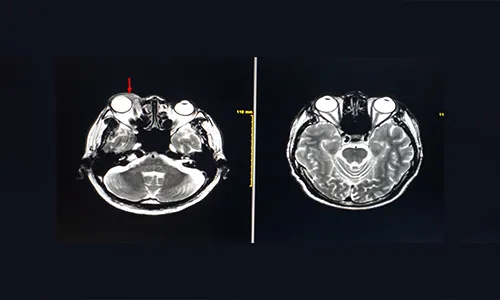

- MRI orbit